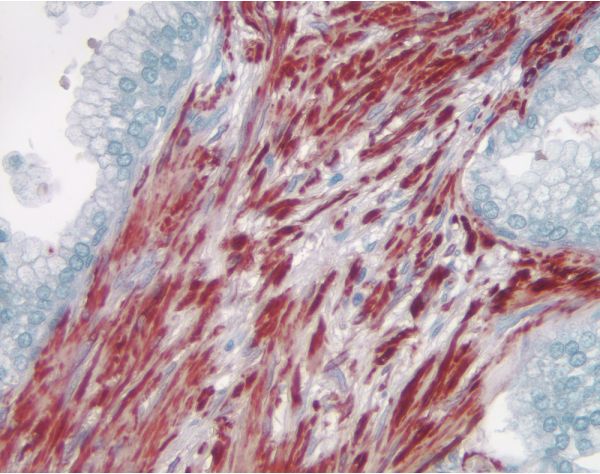

VectaMount AQ Eindeckmedium (VEC-H-5501) ist ein aushärtendes Eindeckmedium, das für die Verwendung mit enzymatischen Substraten, wie AEC, ImmPACT® AEC und ImmPACT AMEC Red, entwickelt wurde, deren Reaktionsprodukte in Alkohol oder anderen organischen Lösungsmitteln löslich sind. Für Anwendungen, bei denen eine wässrige Einbettung bevorzugt wird, ist VectaMount AQ auch für die Verwendung mit anderen Substraten wie DAB, Vector® SG, BCIP/NBT, Vector Red, ImmPACT Vector Red, Vector Blue, ImmPACT DAB, ImmPACT DAB EqV und ImmPACT SG geeignet.